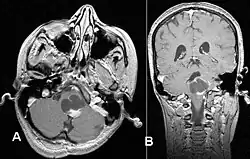

Pilocytic astrocytoma in the hypothalamic region

T1-weighted coronal MRI image postcontrast showing heterogeneous contrast enhancement within the presumed tectal plate glioma